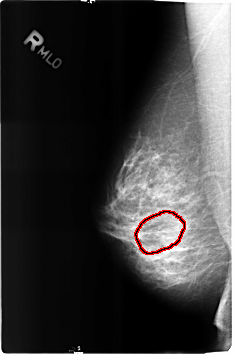

B_3160_1.RIGHT_MLO

FILE: B_3160_1.RIGHT_MLO.OVERLAY

TOTAL_ABNORMALITIES 1

ABNORMALITY 1

LESION_TYPE MASS SHAPE OVAL MARGINS N/A

ASSESSMENT 2

SUBTLETY 3

PATHOLOGY BENIGN

TOTAL_OUTLINES 1

BOUNDARY

RIGHT_MLO LINES 4600 PIXELS_PER_LINE 3032 BITS_PER_PIXEL 12 RESOLUTION 50 OVERLAY